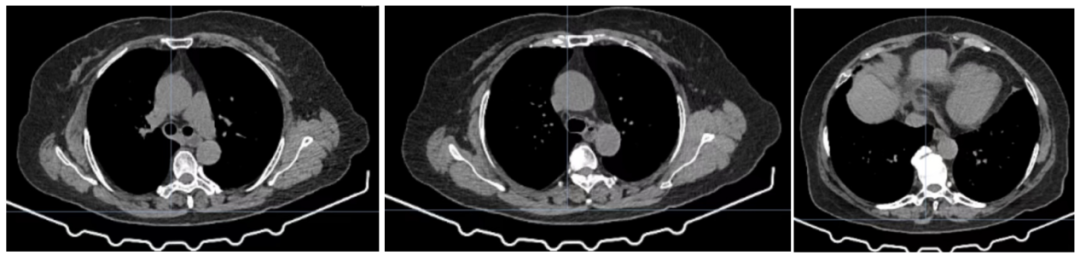

图3. CT复查结果

病例一患者为45岁女性,因“胸闷”于2020年1月就诊。经影像学检查、病理检查

确诊为广泛期小细胞肺癌(cT4N3M1a,ⅣA期)。患者因经济因素入组RATIONALE-312研究,于2021年2月22日起接受研究方案(铂类+依托泊苷联合替雷利珠单抗或安慰剂)治疗。治疗后肿瘤快速缓解,首次疗效评估即达到PR。此后定期进行影像学随访,结果显示疗效持续,病灶控制稳定,PFS已超过40个月,且治疗期间总体安全性可控。